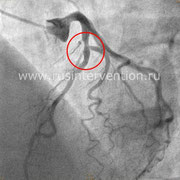

Пациент К., 70 лет, боли за грудиной, чувство нехватки воздуха при физической нагрузке, максимальные цифры артериального давления до 180/90 мм рт.ст., результат нагрузочной пробы (Тредмил-Теста) – проба сомнительная (типичный болевой приступ за грудиной, без изменений на ЭКГ).

Больному проводится коронарография, где выявлен стеноз одной из коронарной артерии около 30-40%, далее этому пациенту определяется ФРК и оказывается, что пограничный стеноз является значимым и требует стентирования, что полностью несоответствует ангиографической картине.

Сравнение коронарографии и коронарографии совместно с определением фракционного резерва кровотока

Данный пример еще раз показывает значимость и необходимость проведения дополнительных диагностических методов в дополнении к стандартной коронарографии.